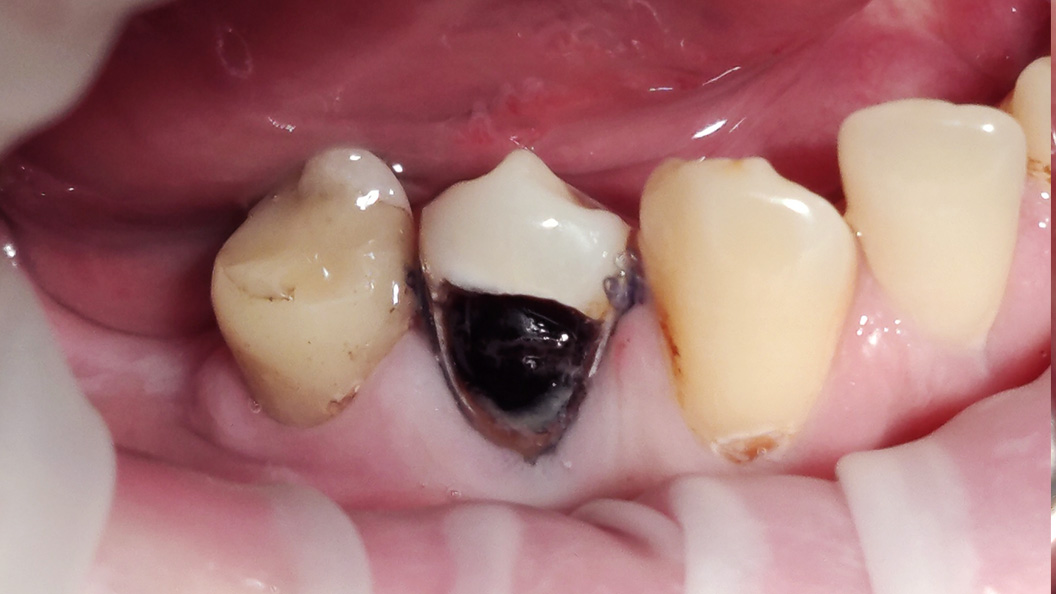

Пациент обратился с жалобой на эстетический недостаток в области нижнего зуба справа. После обработки кариозной полости врач выявил глубокий кариес. Дно и стенки полости плотные, гладкие, блестящие, при зондировании крепетируют. Реакция на холод слабоболезненна, на перкуссию — безболезненна. Диагноз — хронический глубокий кариес.

Ход лечения:

- введение анестезии Sol. Articaini vs. Adrenalini 1:200000 1.8 ml;

- наложение системы OptaGate;

- установка ретракционной нити UltraPack 00;

- механическая обработка кариозной полости;

- медикаментозная обработка полости раствором хлоргексидина 2%;

- пломбирование Vitremer (A3);

- микроконтурирование и макроконтурирование пломбы.